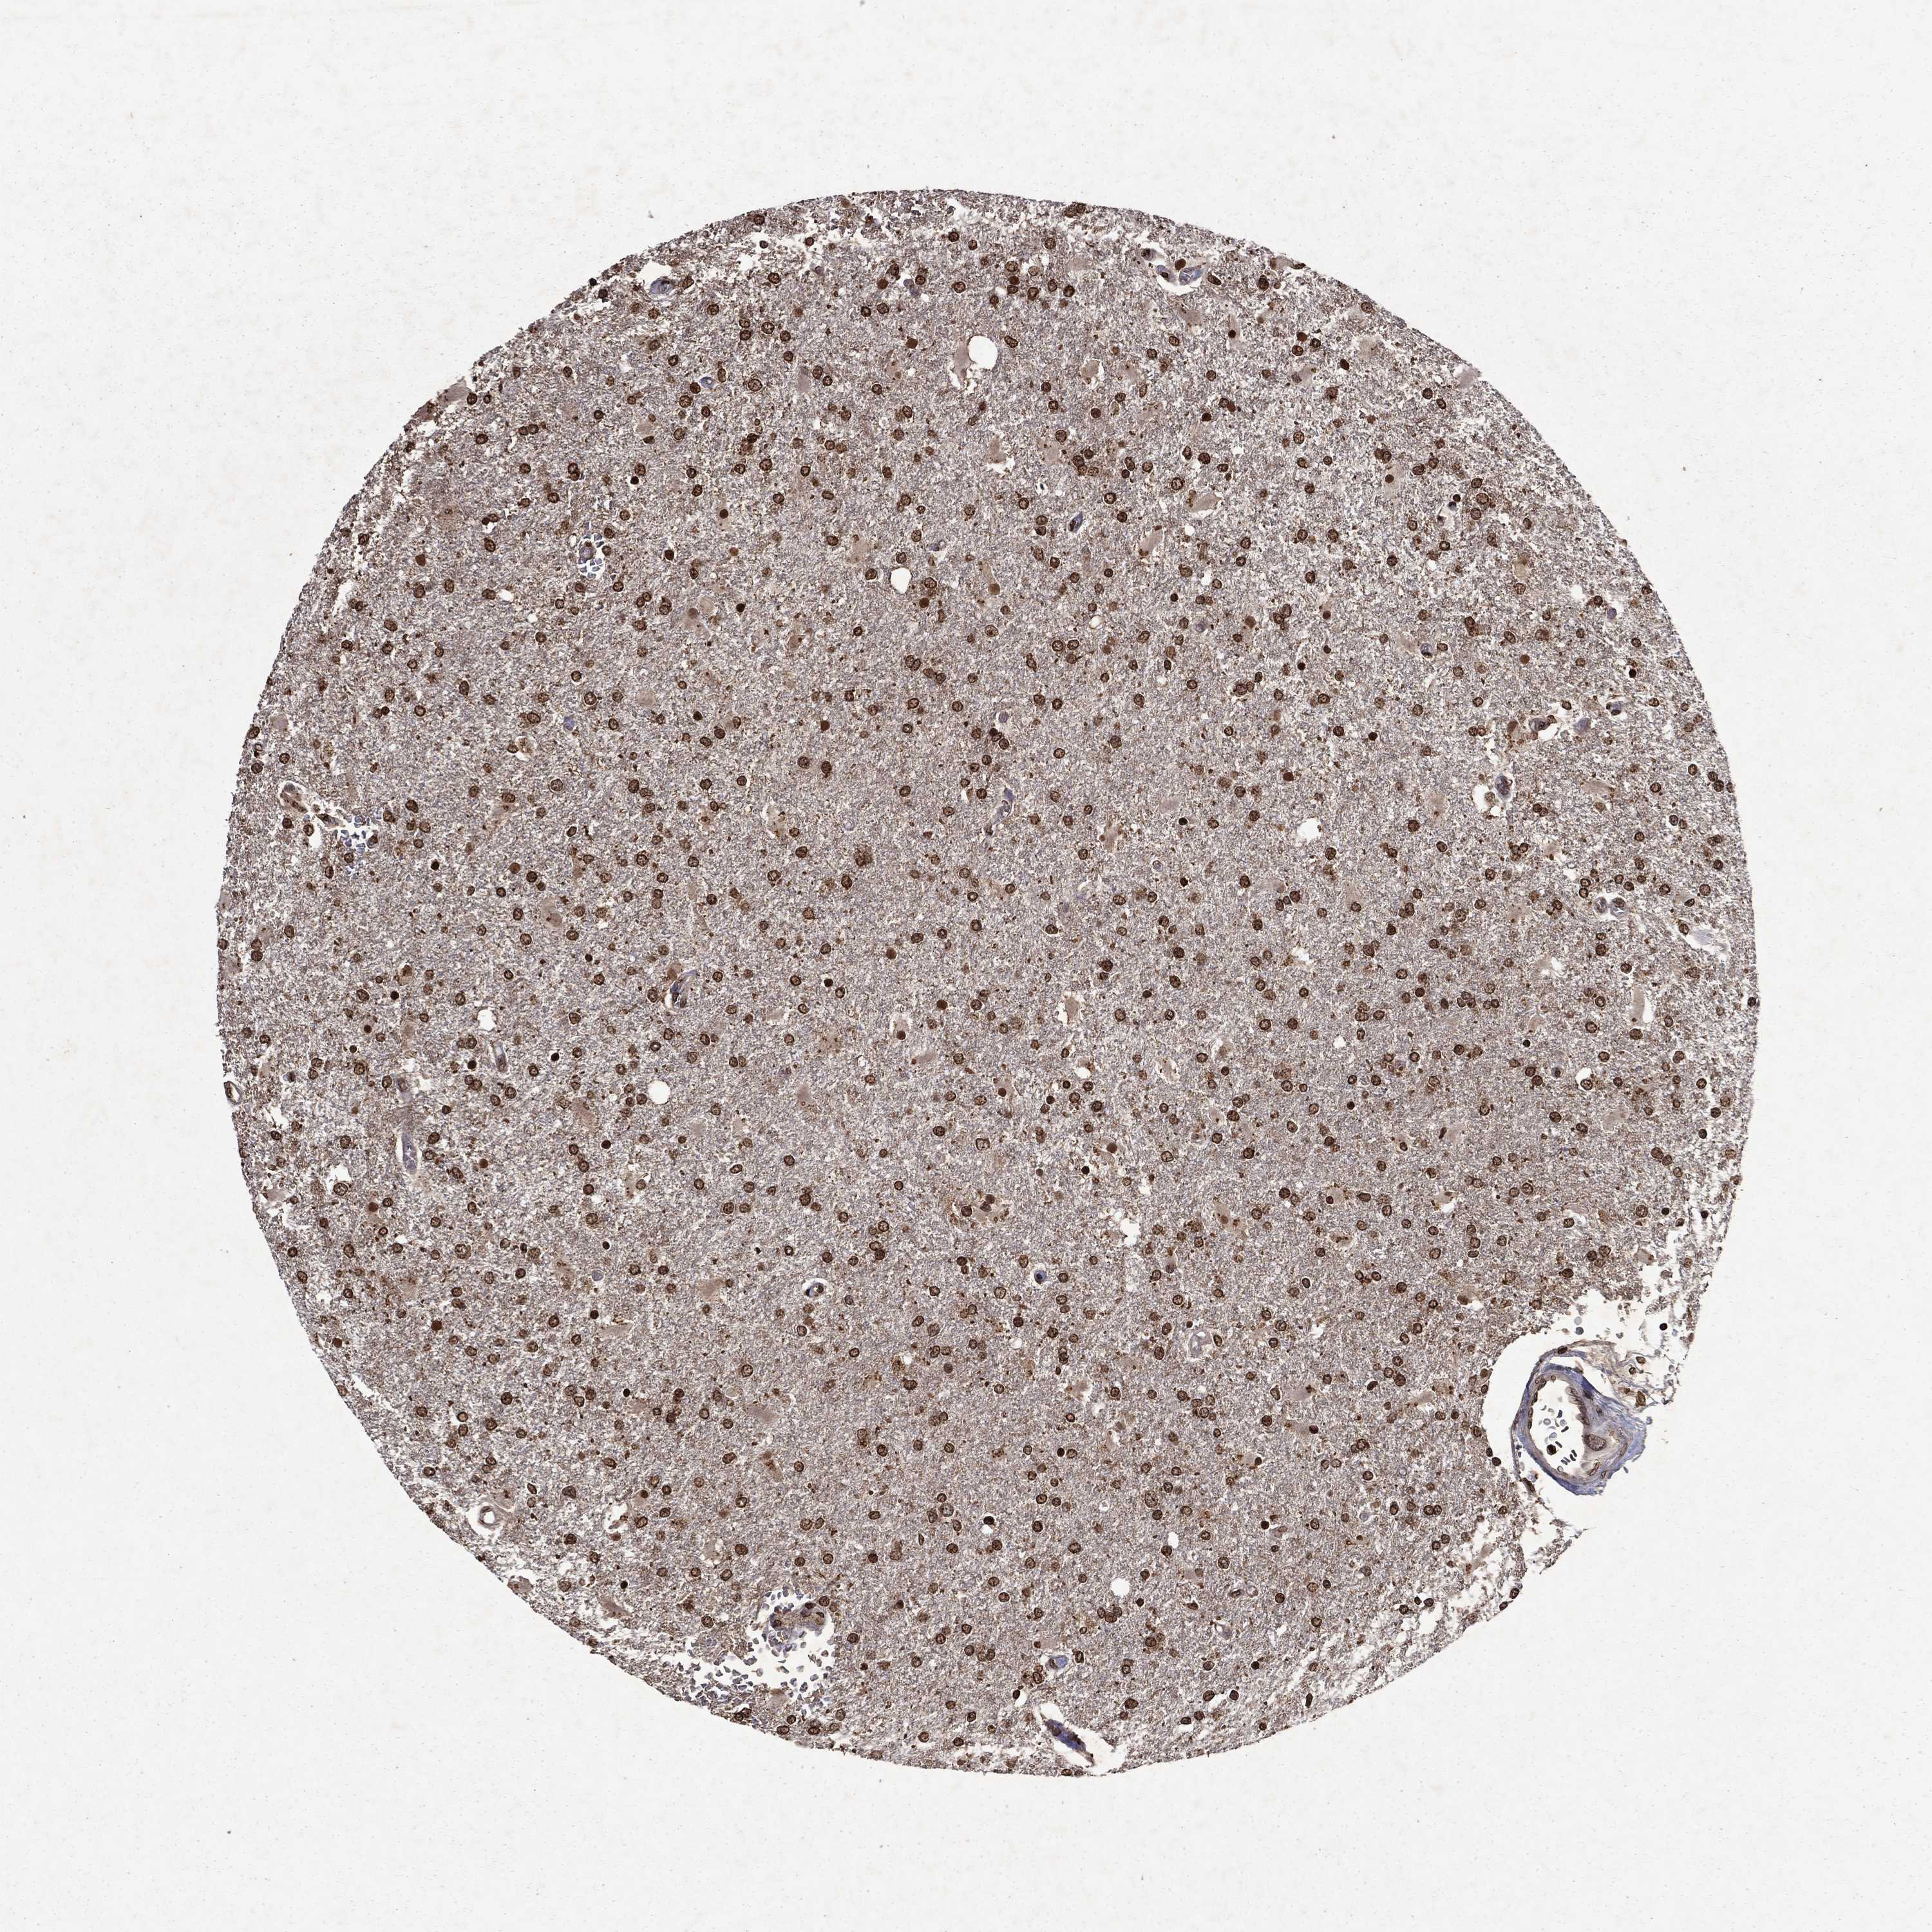

GLIOMA - Protein expressioni

A mouse-over function shows sample information and annotation data. Click on an image to view it in a full screen mode. Samples can be filtered based on level of antibody staining by selecting one or several of the following categories: high, medium, low and not detected. The assay and annotation is described here.

Note that samples used for immunohistochemistry by the Human Protein Atlas do not correspond to samples in the TCGA dataset.

Antibody stainingi

Antibody staining in the annotated cell types in the current human tissue is reported as not detected, low, medium, or high, based on conventional immunohistochemistry profiling in selected tissues. This score is based on the combination of the staining intensity and fraction of stained cells.

Each image is clickable and will lead to virtual microscopy that enables deeper exploration of all samples and also displays staining intensity scores, fraction scores and subcellular localization as well as patient and tissue information for each sample.

Antibody HPA054483

Antibody HPA064504

Staining

High

Medium

Low

Not detected

Intensity

Strong

Moderate

Weak

Negative

Quantity

>75%

75%-25%

<25%

None

Location

Nuclear

Cytoplasmic/membranous

Cytoplasmic/membranous,nuclear

Glioma, malignant, Low grade

Glioma, malignant, High grade

Glioma, malignant, NOS